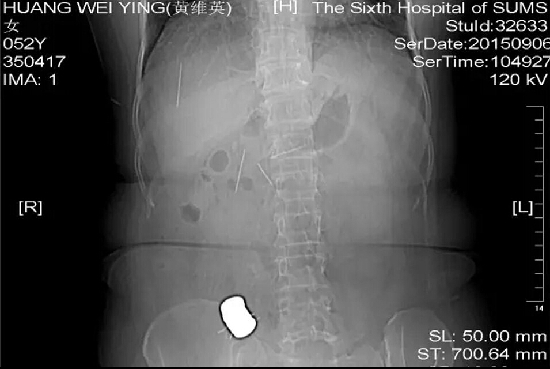

老人腹痛吞下10根绣花针 在广州急救

一开始,黄姨的子女以为她是阑尾炎,马上将她送到当地医院,黄姨在急诊拍了x光片,而X光片的结果就吓了大家一跳,因为黄姨的肚子里面,有好多根针,还导致了多发性肠穿孔。